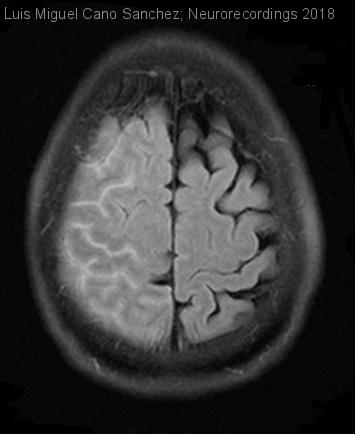

Meningitis crónica de etiología inusual

Mujer | 71 años

Diagnóstico final: Meningitis reumatoide

Resumen del caso

Se trata de una mujer de 71 años dislipémica, con hipotiroidismo y artritis reumatoide (AR) seropositiva de 10 años de evolución, en tratamiento con leflunomida y corticoides a dosis bajas (metilprednisolona 2mg/día). Ingresa por episodios repetidos...